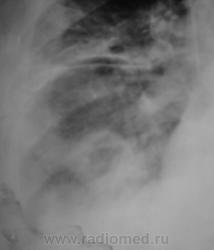

Пациенту в "области" была произведена операция по поводу "аденомы" предстательной железы. Через 3 дня после операции состояние пациента резко ущудшилось, была назначена рентгенография. Снимок ниже.

Валентин Львович! Наверняка перед операцией пациенту выполнялась ФЛГ и там возрастная норма (надеюсь, что это так). Следовательно "аденома" не является причиной изменений в легких. Тогда остается холодная операционная и абсцедирующая пневмония правого легкого.

До операции - "норма".

Но все таки абсцедирующая пневмония!

Думаю, что да - это абсцесс легкого

Объясните мне, не специалисту в пульмонологии, может ли абсцесс сформироваться за 3 дня. Или я что-то не так поняла? Видна дренированная полость, округлая, довольно четко отграниченная. В плевральной полости жидкость.

Уважаемая Nela! Двайте пойдем "логическим путем"(надеюсь, что вместе). Пожилой пациент готовится к плановой операции (аденомэктомии). Насколько мы знаем организацию нашего здравоохранения, перед плановой операцией пациент в амбулаторном порядке проходит кучу предоперационых исследований (анализы крови, мочи, ЭКГ, УЗИ простаты, почек, ФЛГ и т.д.). Если все в порядке и противопоказаний к оперативному вмешательству не имеется, пациента берут на операцию. Если имеются малейшие отклонения - то до их устранения. Если противопоказания не устранимы - пациенту в плановой операции может быть отказано. Пациента на операцию взяли, т.е. все в порядке, в том числе и в легких. Через три дня после операции мы видим представленную рентгенологическую картину. Деструкция легочной ткани. Абсцедирующая пневмония, абсцесс легкого. Смею Вас заверить, по собственному опыту, и у пациентов зрелого возраста и у молодых пациентов в послеоперационном периоде (3-5 дней) возможно развитие осложнения послеоперационного периода в виде пневмоний, в том числе абсцедирующих. Причина - чаще всего внутрибольничный стафилококк. Операция - ослабление иммунитета- внутрибольничная (очень злая, доморощенная, устойчивая к антибиотикам) стафилококковая инфекция. Вот и  пришли к конечной точке нашего пути.